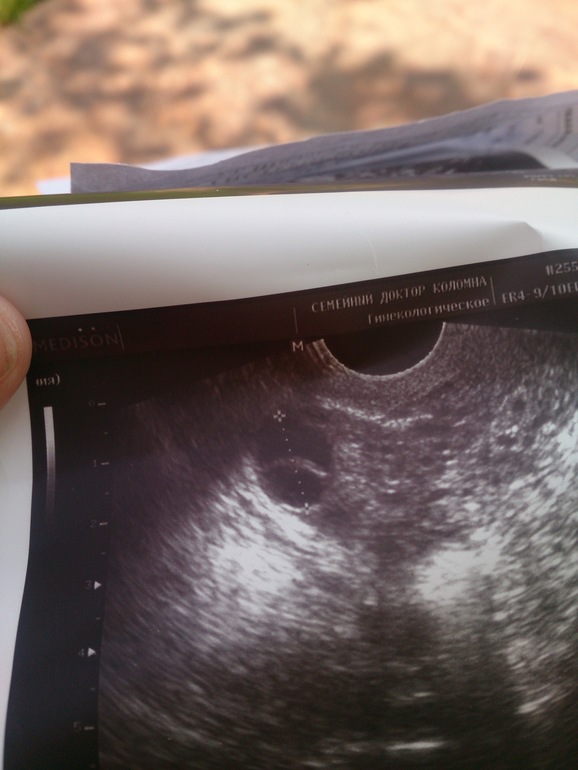

Ходила на узи 15дц, мне сказали,что ДФ нет, есть только 17мм кистозно измененный с перегородкой, он деформирован,приплюснутый, его она не считает соответственно. Я спросила, ну а если он совулирует и спермики доберутся до него,как скажется это на ребенке? Г ответила,что его нельзя оплодотворить,так как яйцеклетка то-ли плохая,то-ли ее нет,это уже я не поняла. Но мне интересно Ваше мнение, может кто что знает? Фото постараюсь выложить.